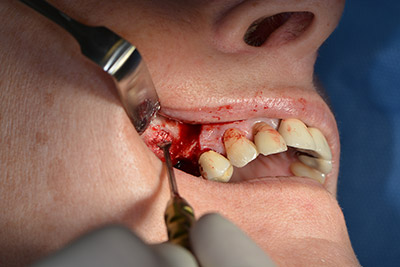

The next step was the sinus floor elevation with simultaneous implantation. The Implantmed also had a presetting at the first position for the buccal fenestration of the maxillary sinus wall.

The fenestration was prepared at 35,000 rpm and then the nasal mucosa were prepared in the cranial direction (Fig. 13 to 14).

preparation of the nasal mucosa

Image 13

Inclined drilling

Image 14